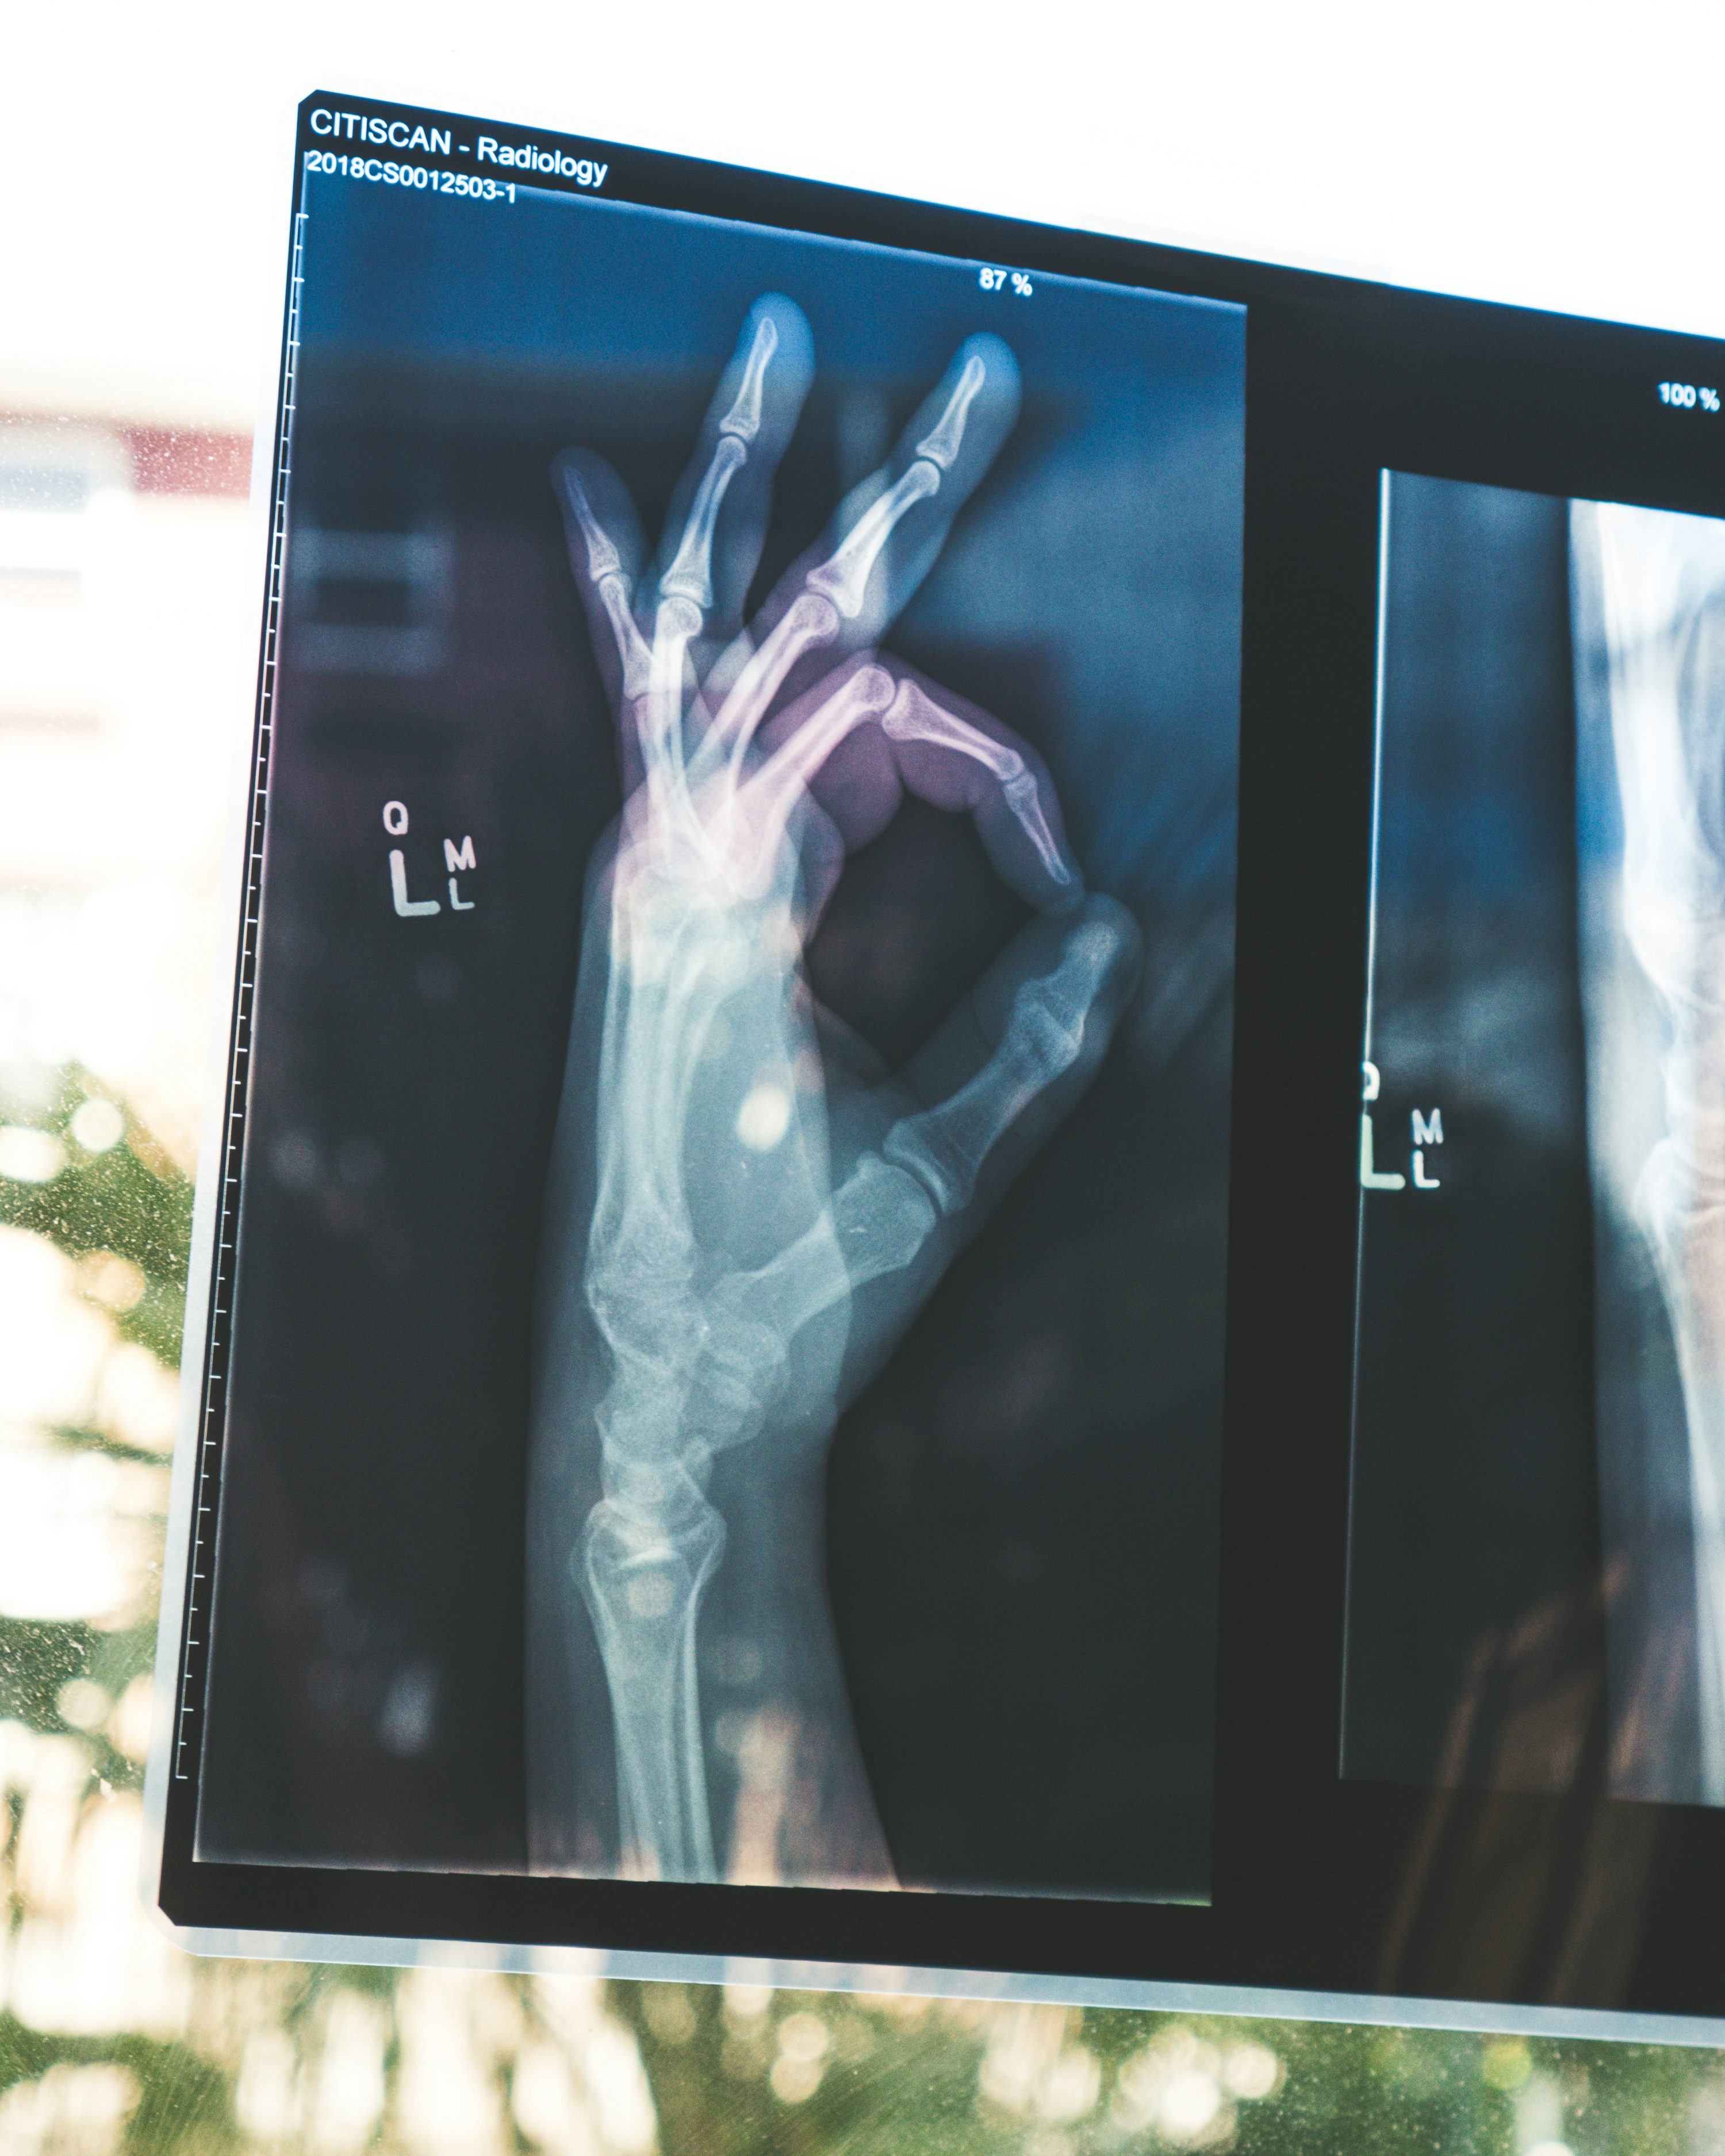

① 진단 기반 치료 단순한 통증만의 치료가 아닌, 영상(엑스레이, MRI), 혈액 검사 등의 진단이 먼저여야 한다. 왜냐하면 연골 마모인지, 인대 손상인지, 혹은 관절염 초기인지에 따라 치료 방향이 달라지기 때문이다.